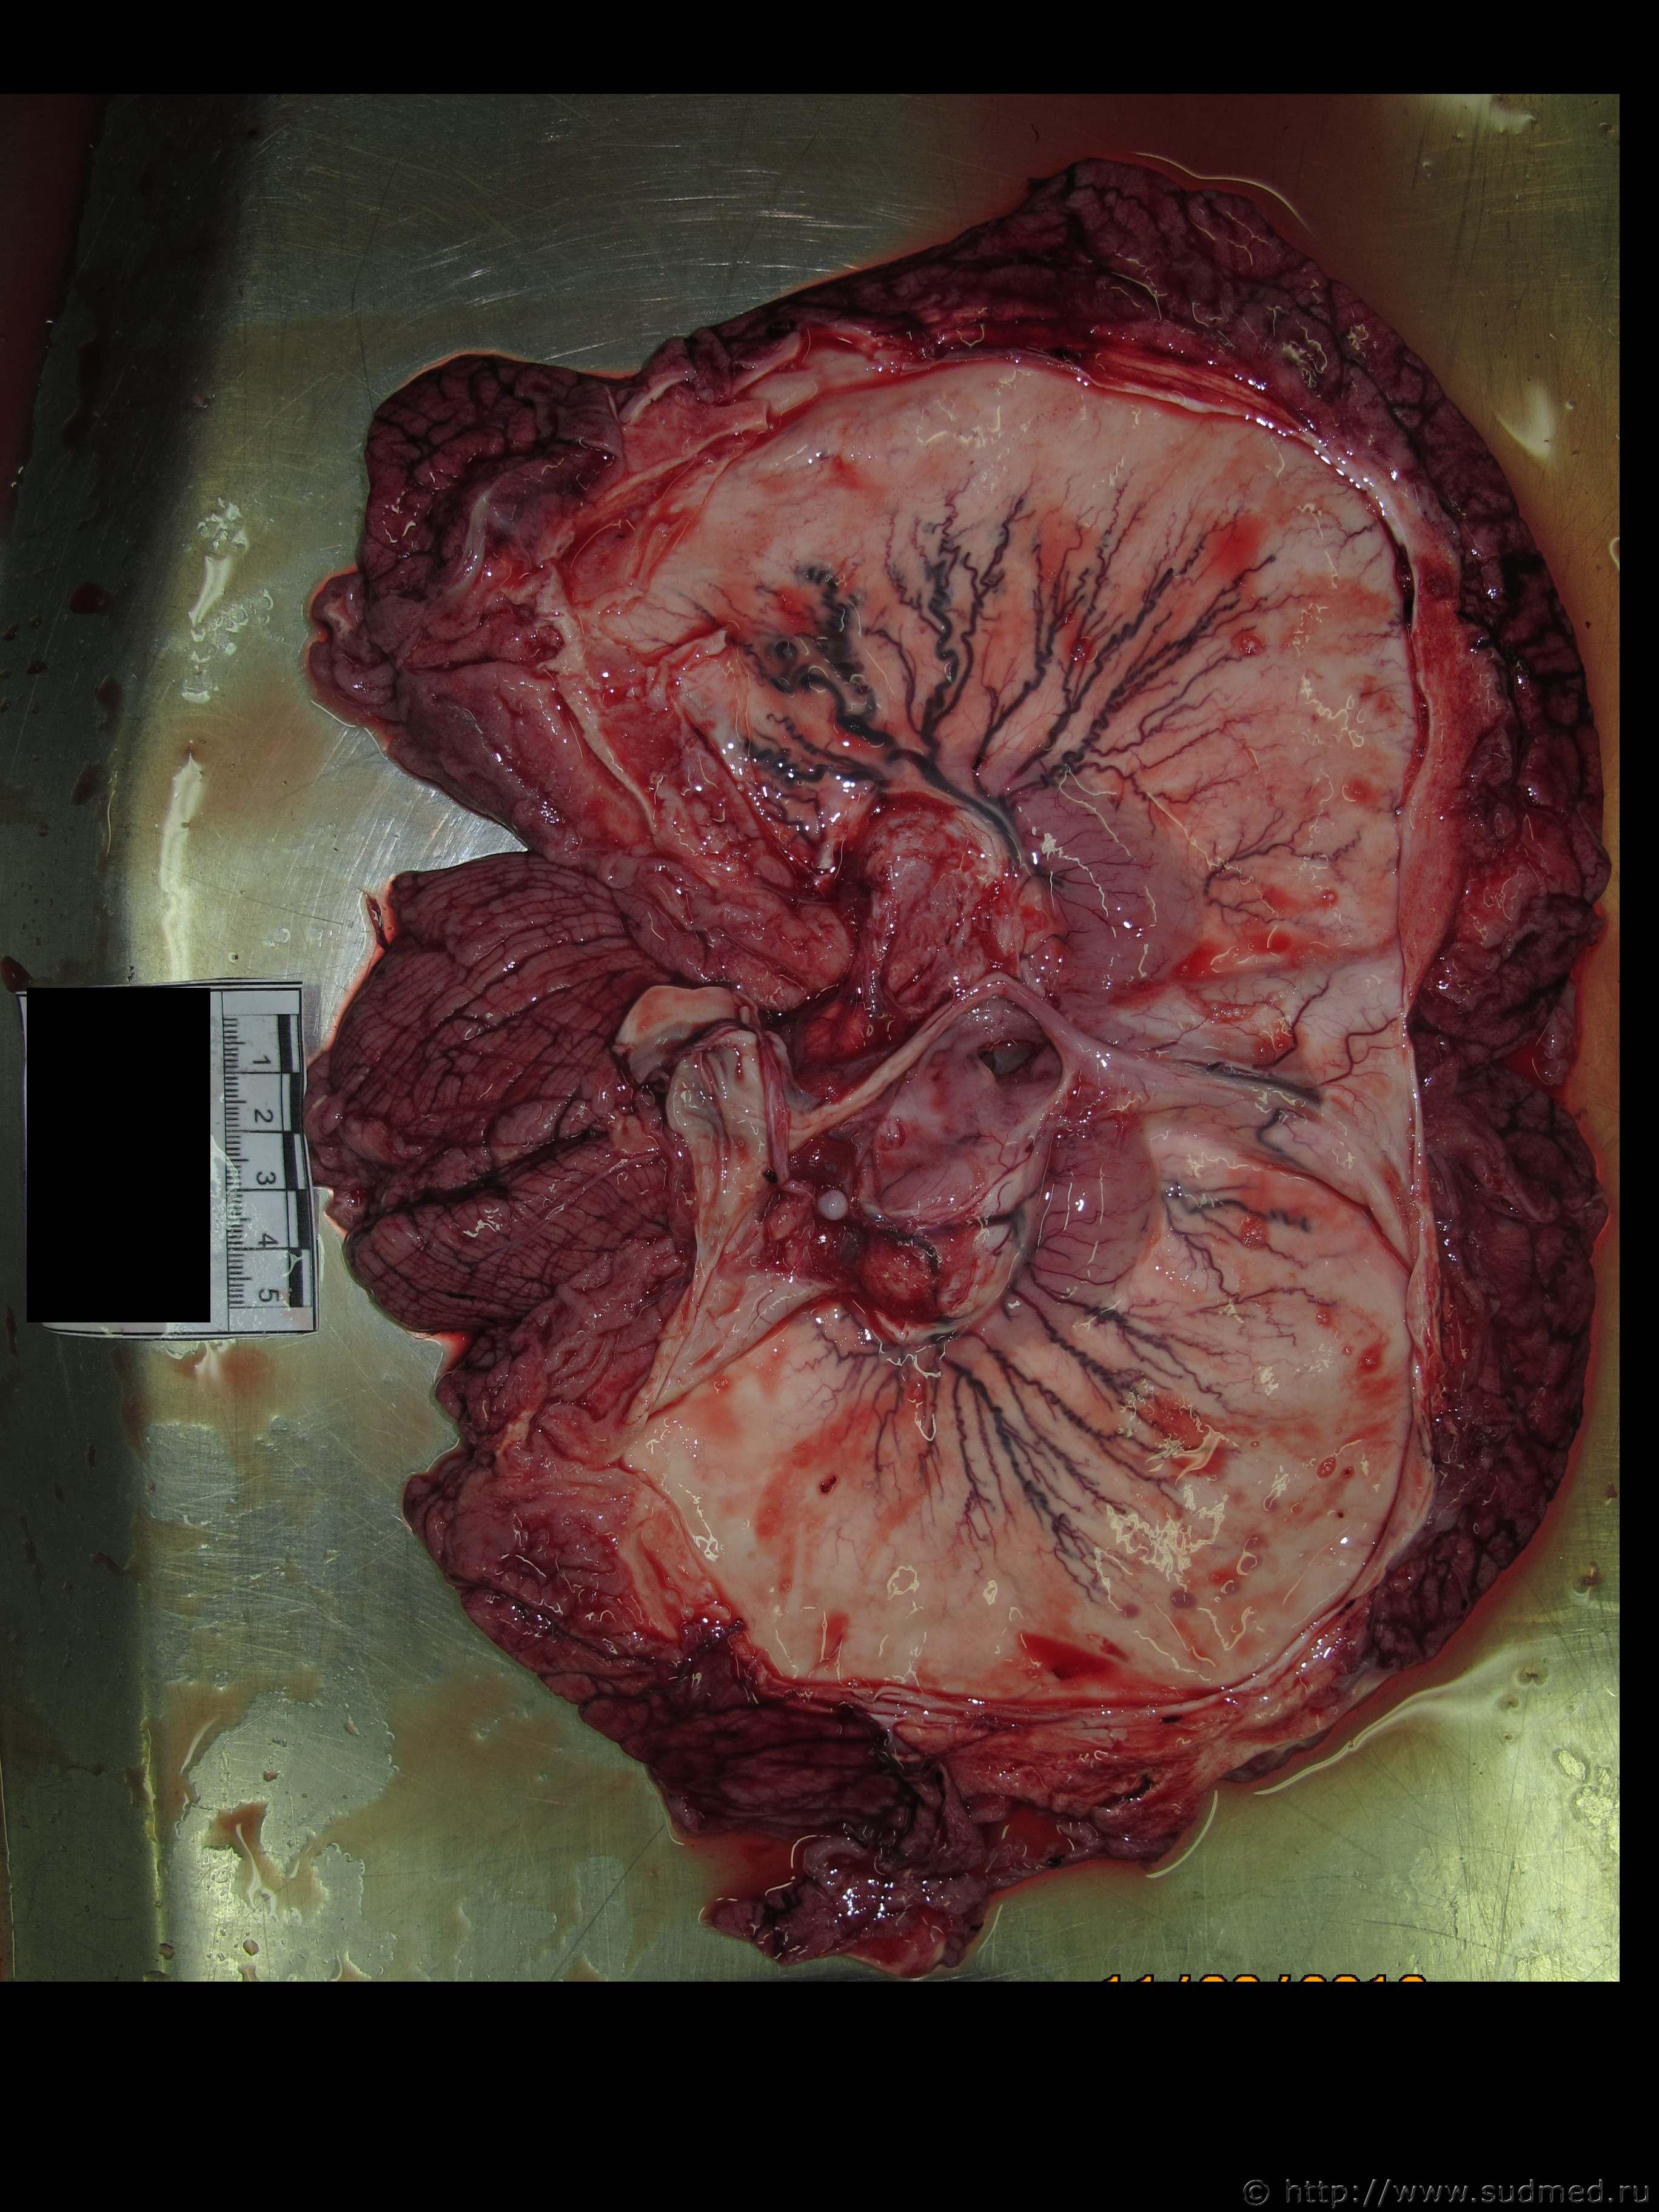

Светлоклеточный тип почечноклеточного рака.

Эскизы прикрепленных изображений